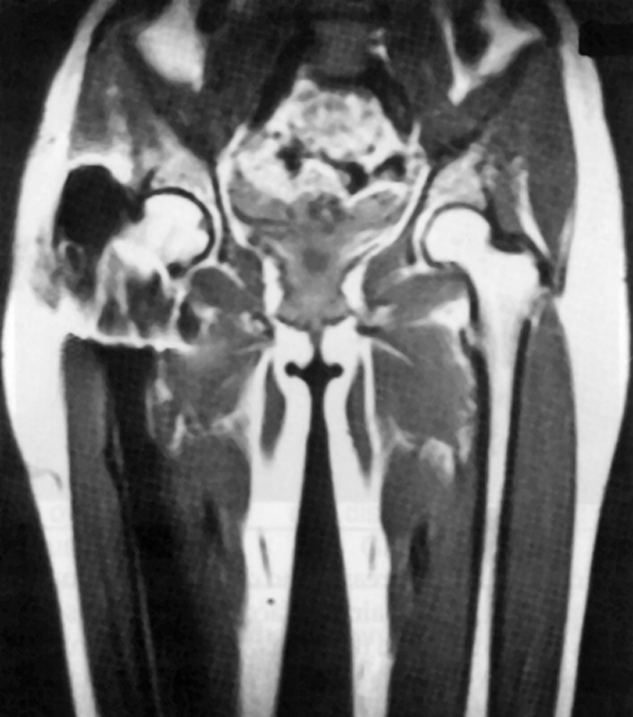

Figure 17-04:

Artifacts resulting from the presence of ferromag­netic material. Signal loss and signal dis­tor­tion as­so­­ci­a­ted with a fer­ro­mag­ne­tic prosthesis in the right leg.